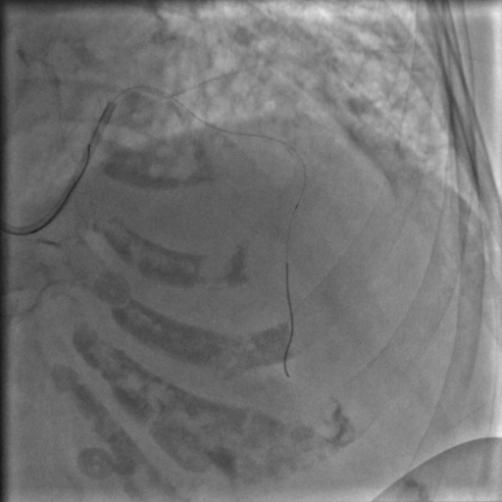

好像又出来多一点了,那就再用球囊扩一下吧,但是怎么判断远端是不是在主支和真腔里呢?

主刀的大师兄这时候突然间灵机一动,提出了一个很有创造性的做法。

我们知道,做CTO的手术有时候会从微导管里面打造影剂判断远端导丝是不是在真腔里,那我们是不是也可以效仿,把旧球囊刺破,再将旧球囊送到远端,往里面打造影剂。

图13

没错,导丝远端确实是在主支真腔里,那可以再放心大胆地用球囊来扩张了,送入球囊,从远端一直往回扩,这次因为底气足了,所以比上次走得更远、扩张得更加充分,压力最大打到了10个大气压。

图14

造影:

图15

彻底绝望,这是什么血栓这么顽固!